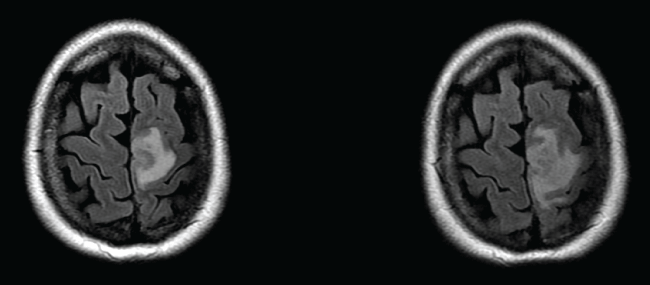

MRI of the entire spine (to exclude infliximab-induced demyelination) was normal. Repeat CT brain with contrast excluded sinus thrombosis but showed subtle low attenuation in the white matter at the vertex of the left frontoparietal junction without definite enhancement; in retrospect, this was discernible on the admission CT. Expedited MRI brain (Figure 1) confirmed a left frontal cortex abnormality consistent with a cerebral abscess, in addition to further regions of early abscess formation in the left frontal and left temporal lobes. Lumbar puncture was unremarkable (cells, protein, glucose, microscopy and culture). Ceftriaxone 2 g twice daily, and Metronidazole 500 mg twice daily were commenced intravenously after blood cultures were taken from the afebrile patient. The regimen was modified to Ampicillin 8 g daily and Gentamicin 1mg/kg three times daily intravenously after Listeria monocytogenes was cultured from the blood. Methotrexate and Infliximab were ceased but Prednisolone 10mg daily was continued. Gentamicin was administered for 3 weeks, followed by Benzylpenicillin by Baxter pump for 2 months followed by Sulfamethoxazole/Trimethoprim for 4 months.

Figure 1: MRI brain at similar level on day 2 (left) and 9 (right) post admission. Early abscess/cerebritis of the left medial frontal lobe is apparent.

Neurologic function and MRI imaging began to improve about three weeks after commencement of antibiotics. Lower limb function had recovered fully by 5 months post presentation, and the Crohn's disease remained in remission on Mesalazine 2 g twice daily and Prednisone 7.5 mg daily. The patient has been advised to avoid unpasteurised dairy products.